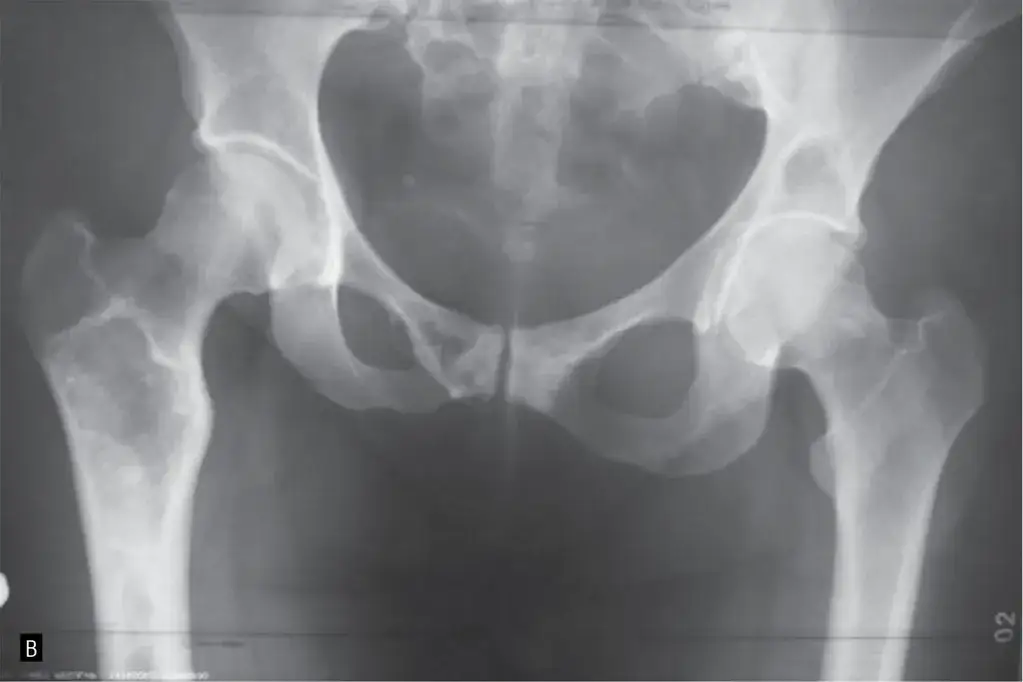

Wykrycie ognisk osteolitycznych wymaga specjalistycznych badań obrazowych. Standardowe zdjęcie rentgenowskie często nie wystarcza, ponieważ zmiany te mogą być niewidoczne na wczesnym etapie. Dlatego lekarze sięgają po bardziej zaawansowane metody, takie jak tomografia komputerowa czy rezonans magnetyczny.

RTG to podstawowe badanie, które może wykazać większe ogniska osteolityczne, ale często nie jest wystarczające na wczesnym etapie. Jest to jednak szybka i dostępna metoda, która może być pierwszym krokiem w diagnostyce.

Tomografia komputerowa (TK) i rezonans magnetyczny (MRI) są znacznie dokładniejsze. TK pozwala na szczegółowe zobrazowanie kości, podczas gdy MRI lepiej pokazuje zmiany w tkankach miękkich. Oba badania są niezbędne w przypadku podejrzenia przerzutów nowotworowych.